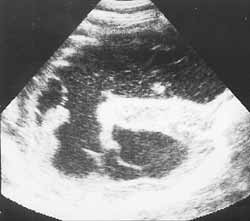

Ультразвуковая диагностика гнойных менингитов у детей первого года жизни.

Рис. 3. Клебсиелезный менингит. (Слева) Некротические массы ткани мозга в острый период. (Справа) Стадия формирования гидроцефалии.